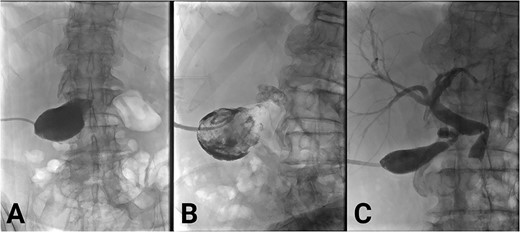

Bloods on admission revealed the following: haemoglobin (Hb) 141 (130–180 g/L), white cell count (WCC) 23.7 (4–11 × 109/L), bilirubin total/direct 35/25 (<20/<7 μmol/L), alkaline phosphatase (ALP) 383 (30–110 U/L), gamma-glutamyl transferase (GGT) 267 (<55 U/L), alanine transaminase (ALT) 738 (<35 U/L), and aspartate aminotransferase (AST): 884 (<40 U/L). Initial imaging suggested acute cholecystitis; ultrasound (US) showed a distended gallbladder with a thickened wall (Fig. 1A), and non-contrast computed tomography (CT) showed a distended gallbladder with pericholecystic stranding (Fig. 1B). One day later, magnetic resonance cholangiopancreatography (MRCP) showed cholecystitis, biliary duct dilatation, and choledocholithiasis (Fig. 1C). No cholelithiasis was present. Blood cultures were positive for Escherichia coli.

(A) Ultrasound scan showing a distended and enlarged gallbladder with a thickened wall suggestive of acute cholecystitis. No obvious gallstones are present. (B) Reconstructed contrast-enhanced coronal CT shows an enlarged and distended gallbladder, a thickened gallbladder wall, pericholecystic fluid, and a dilated common hepatic duct. (C) MRCP showing an obstructed gallstone at the confluence of the common hepatic duct, common bile duct and cystic duct (marked with arrow).